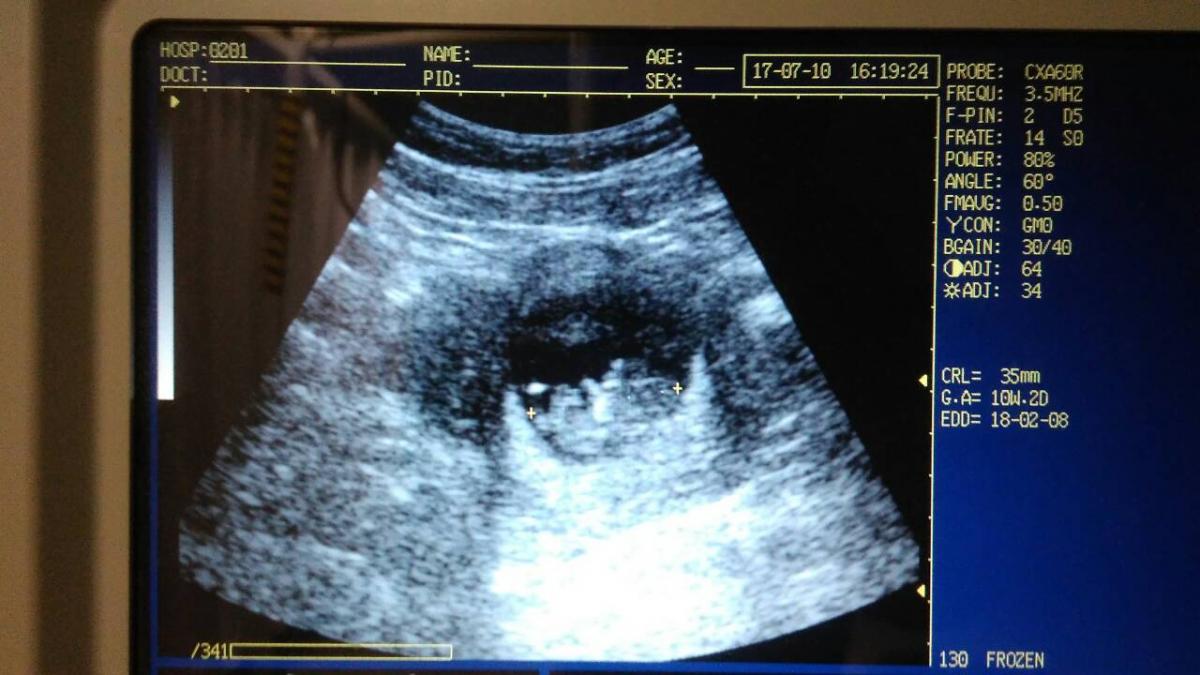

kíváncsi vagyok hétfőn mekkora lesz :) 10-én volt 35 milis :)

En voltam ma dokinal, minden tokeletes, van egy 2,27 cmes tancolo, integeto babacskank <3

A kep sz@r, nem tudom, hogy kiveheto-e vagy csak en latom, de mar rendes baba formaja van, fejjel lefele fekszik, kis denever :-)

Nagyon csodalatos volt latni, ahogy mocorgott. Azt kivanom, hogy itt mindenki minel hamarabb megtapasztalja ugyanezt.

Annyira édes :) teljesen jól kivehető kisbaba forma :) hányadik hétben is vagy?

Mutymurutty, Eszter, koszonom szepen :-) 9 hetes :-)